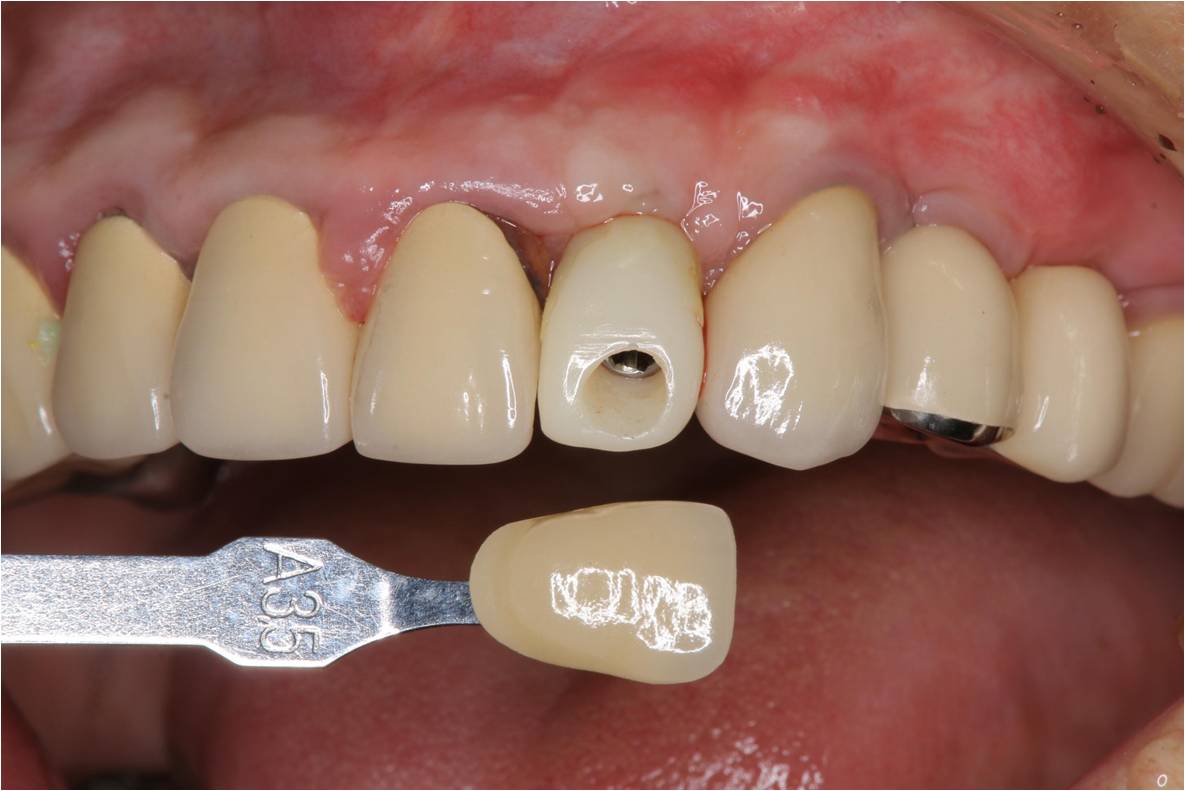

照相比色

氧化鋯釘柱與金屬燒付瓷牙